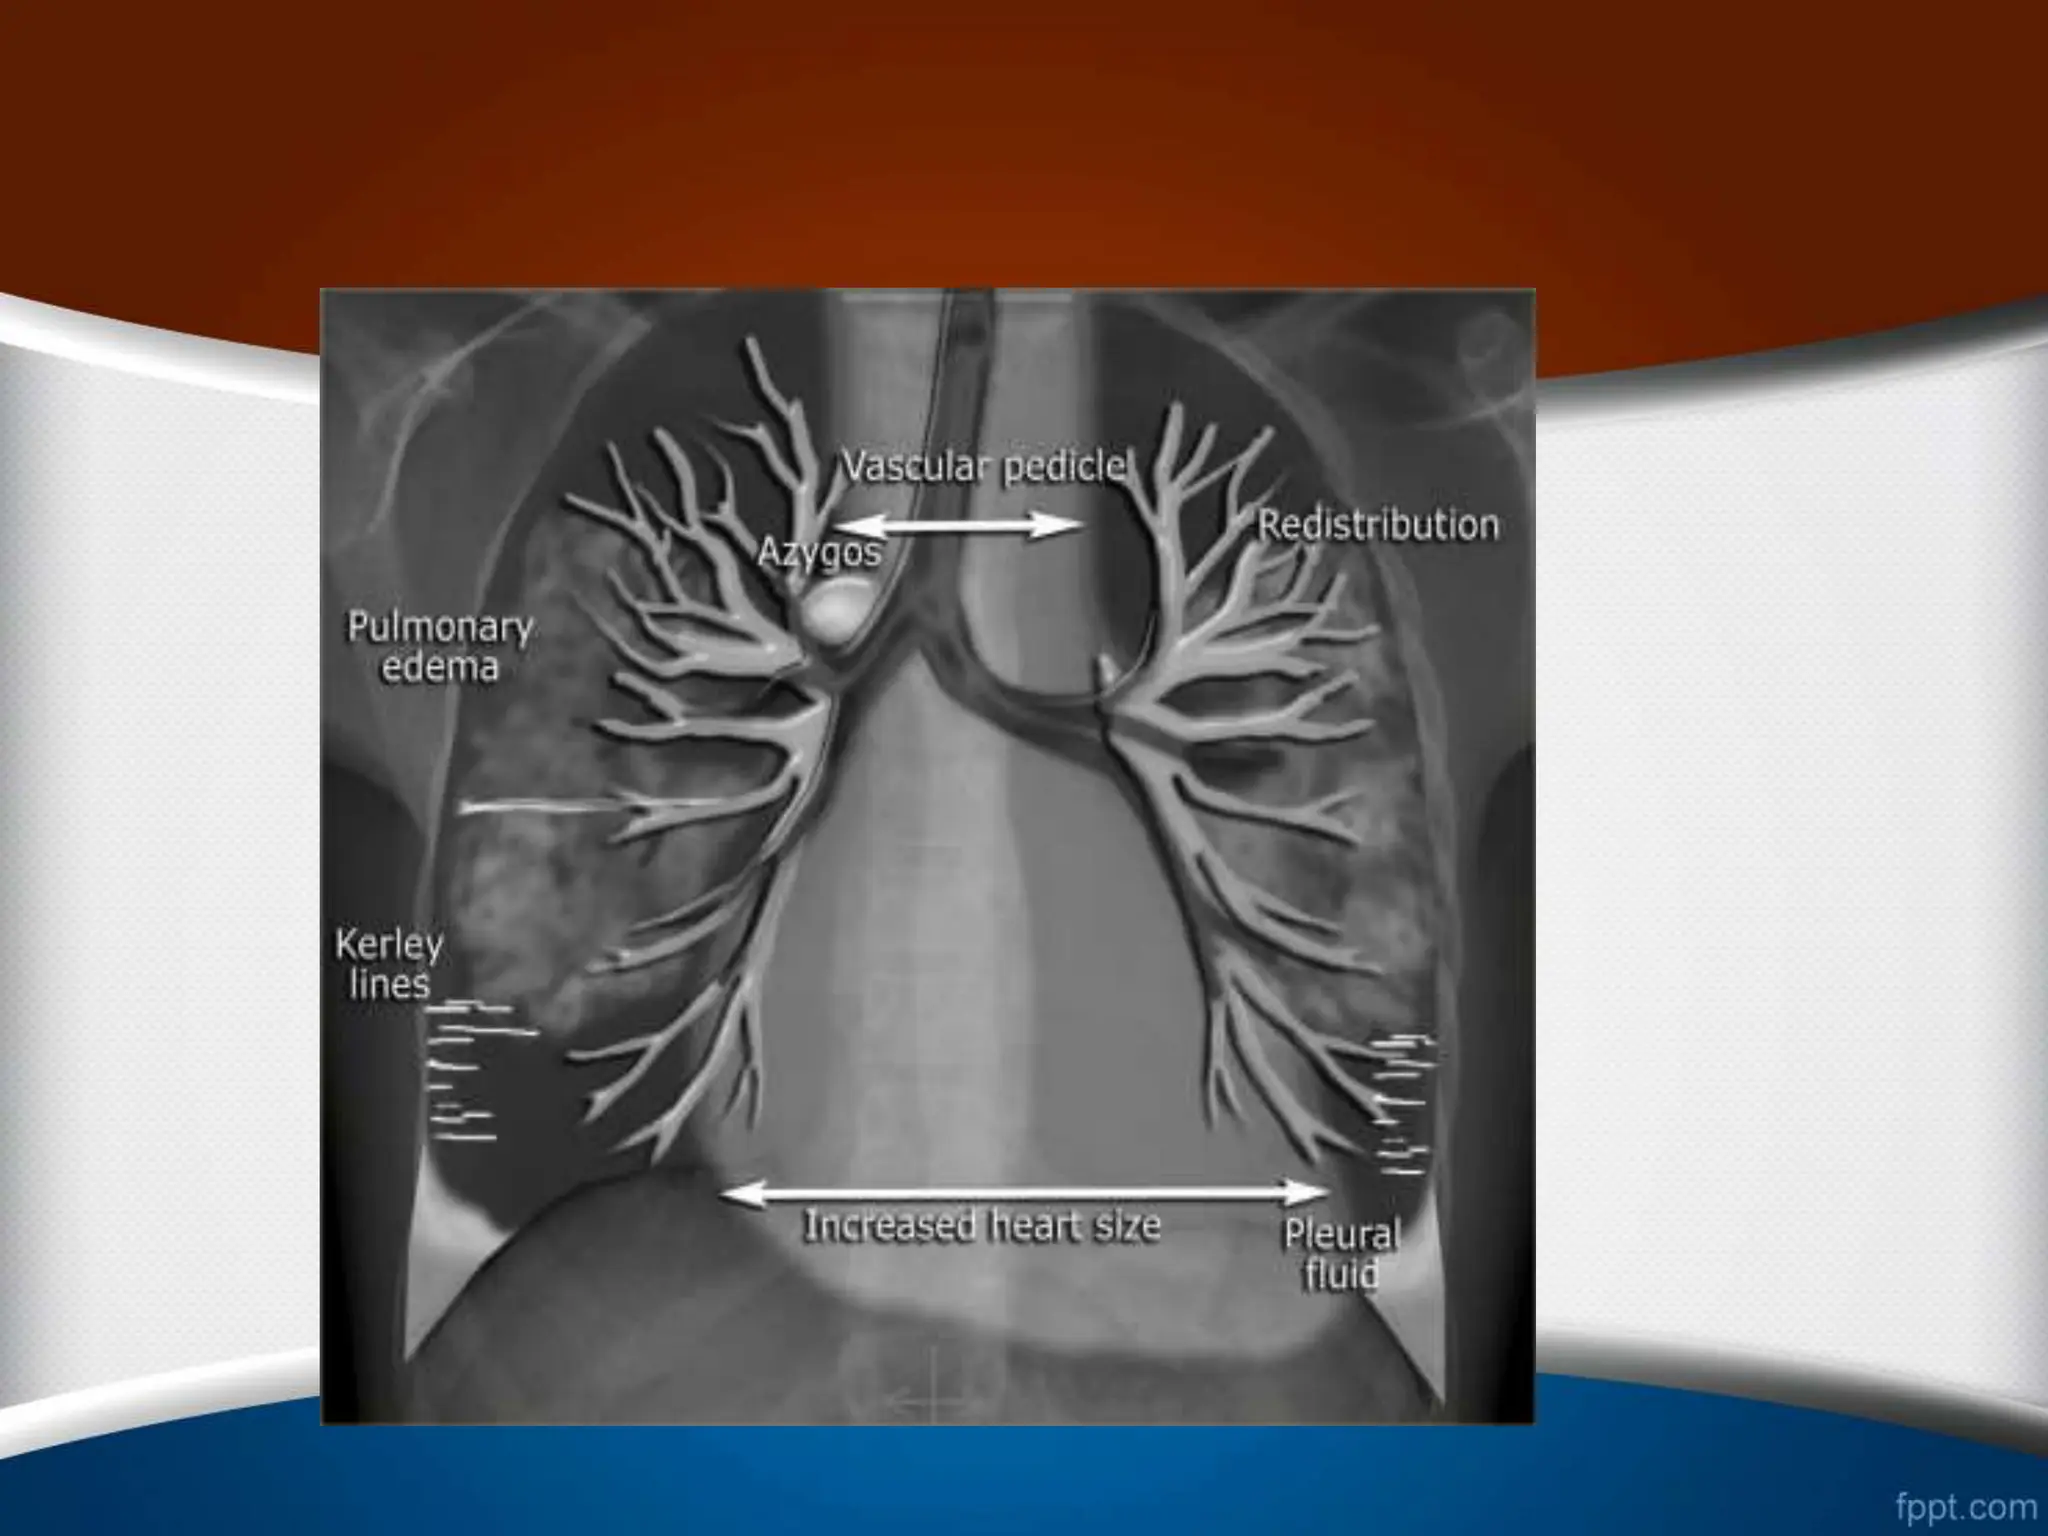

‫یا‬ ‫ریوی‬ ‫وریدی‬ ‫هیپرتانسیون‬

Post Capillary Pulmonary Hypertension - Pulmonary

venous hyper tension

1

.

‫خون‬ ‫جریان‬ ‫مجدد‬ ‫توزیع‬ ‫اول‬ ‫مرحله‬

•

‫که‬ ‫حالتی‬ ‫در‬

Redistribution

‫نسبت‬ ‫دهد‬ ‫می‬ ‫رخ‬

A/B

‫ج‬ ‫بهترین‬ ‫و‬ ‫یابد‬ ‫می‬ ‫افزایش‬ ‫میانی‬ ‫و‬ ‫فوقانی‬ ‫لوب‬ ‫در‬

‫برای‬ ‫ا‬

‫است‬ ‫ریه‬ ‫ناف‬ ‫اطراف‬ ‫ی‬ ‫ناحیه‬ ‫آن‬ ‫ی‬ ‫مشاهده‬

‫سفالیزاسیون‬

2

‫اینترستیسیل‬ ‫ادم‬

‫م‬ ‫برونکیال‬ ‫پری‬ ‫اینترلوبوالر‬ ‫فضای‬ ‫به‬ ‫مایع‬ ‫نشت‬

‫شخص‬

‫شود‬ ‫می‬

‫اینترلوبوالر‬ ‫فضاهای‬ ‫به‬ ‫مایع‬ ‫این‬ ‫که‬ ‫وقتی‬

‫عنوان‬ ‫تحت‬ ‫کند‬ ‫می‬ ‫نشت‬ ‫محیطی‬

‫کرلی‬ ‫خطوط‬

B

‫مشخص‬

Kerley B

:

‫کرلی‬ ‫خطوط‬ ‫واقع‬ ‫در‬

‫تا‬ ‫یک‬ ‫افقی‬ ‫خطوط‬

‫ی‬ ‫زاویه‬ ‫نزدیک‬ ‫و‬ ‫ریه‬ ‫محیط‬ ‫در‬ ‫متر‬ ‫سانتی‬

‫هستند‬ ‫عمود‬ ‫پلور‬ ‫به‬ ‫که‬ ‫باشند‬ ‫می‬ ‫کوستوفرنیک‬

3

‫آلوئوالر‬ ‫ادم‬

‫یا‬ ‫ریوی‬ ‫وریدی‬‫هیپرتانسیون‬ Post Capillary Pulmonary Hypertension - Pulmonary venous hyper tension 1 . ‫خون‬ ‫جریان‬ ‫مجدد‬ ‫توزیع‬ ‫اول‬ ‫مرحله‬ • ‫که‬ ‫حالتی‬ ‫در‬ Redistribution ‫نسبت‬ ‫دهد‬ ‫می‬ ‫رخ‬ A/B ‫ج‬ ‫بهترین‬ ‫و‬ ‫یابد‬ ‫می‬ ‫افزایش‬ ‫میانی‬ ‫و‬ ‫فوقانی‬ ‫لوب‬ ‫در‬ ‫برای‬ ‫ا‬ ‫است‬ ‫ریه‬ ‫ناف‬ ‫اطراف‬ ‫ی‬ ‫ناحیه‬ ‫آن‬ ‫ی‬ ‫مشاهده‬ . • ‫سفالیزاسیون‬

• 2 . ‫اینترستیسیل‬ ‫ادم‬ • ‫م‬ ‫برونکیال‬‫پری‬ ‫اینترلوبوالر‬ ‫فضای‬ ‫به‬ ‫مایع‬ ‫نشت‬ ‫شخص‬ ‫شود‬ ‫می‬ . ‫اینترلوبوالر‬ ‫فضاهای‬ ‫به‬ ‫مایع‬ ‫این‬ ‫که‬ ‫وقتی‬ ‫عنوان‬ ‫تحت‬ ‫کند‬ ‫می‬ ‫نشت‬ ‫محیطی‬ ‫کرلی‬ ‫خطوط‬ B ‫مشخص‬ ‫شود‬ ‫می‬ . • Kerley B : ‫کرلی‬ ‫خطوط‬ ‫واقع‬ ‫در‬ B ‫تا‬ ‫یک‬ ‫افقی‬ ‫خطوط‬ 2 ‫ی‬ ‫زاویه‬ ‫نزدیک‬ ‫و‬ ‫ریه‬ ‫محیط‬ ‫در‬ ‫متر‬ ‫سانتی‬ ‫هستند‬ ‫عمود‬ ‫پلور‬ ‫به‬ ‫که‬ ‫باشند‬ ‫می‬ ‫کوستوفرنیک‬ -